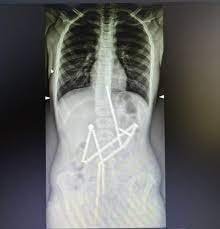

Перший рентген показав присутність численних інородних тіл у травному тракті дитини. Магніти, розташовані в різних частинах шлунково-кишкового тракту, були з'єднані між собою, що викликало занепокоєння серед медичного персоналу.

Більшість магнітів (18 із 20) було витягнуто за допомогою ендоскопічної процедури, але один довелось діставати хірургічним шляхом. Під час лапаротомії було проведено детальний огляд органів черевної порожнини, де і було виявлено п'ять перфоративних отворів і останній магніт, які були успішно оброблені та видалені.